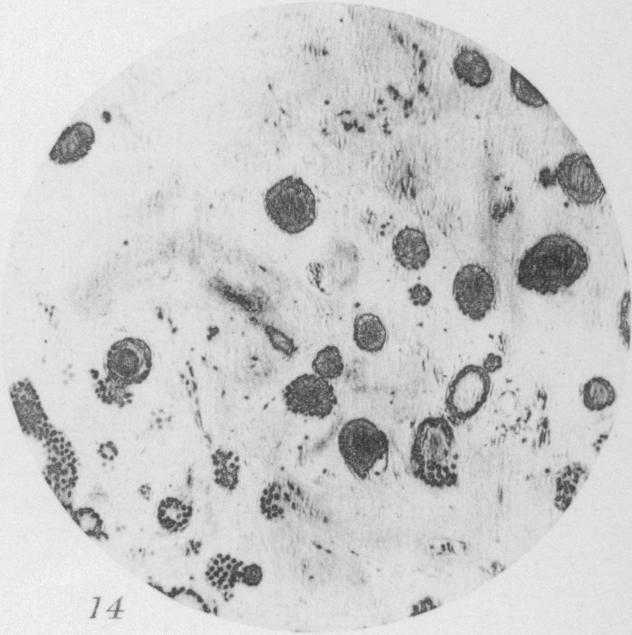

Benign Epithelial tumors of the Thyroid Gland.

J Med Res. 1913 Jan;27(3):229-268.5.